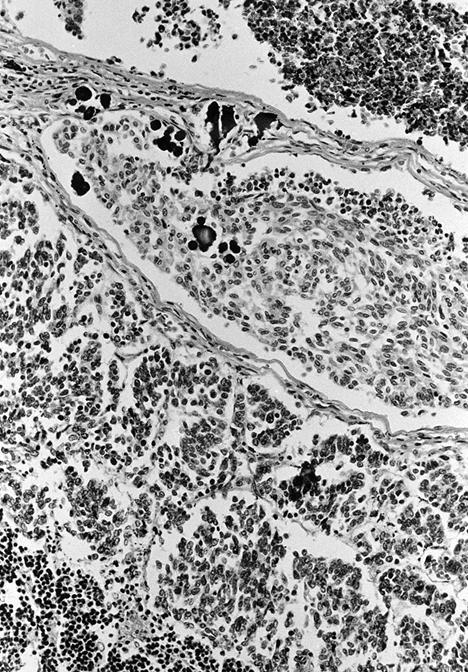

Microscopic (histologic) description

- Wide variety of morphology, can mimic any other thyroid malignancy

- Stroma has amyloid deposits from calcitonin, prominent vascularity with glomeruloid configuration or long cords of vessels (Am J Surg Pathol 1995;19:642), coarse calcifications, occasional psammoma-like bodies

- Often angiolymphatic invasion

- May entrap follicles

- C cell hyperplasia present in familial but not sporadic cases

Microscopic (histologic) images

Contributed by Shuanzeng Wei, M.D., Ph.D., Joseph Christopher Castillo, M.D. and Mark R. Wick, M.D.

AFIP images